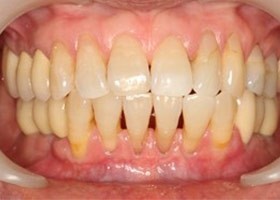

治療前全口x光片、口內照片

術前缺牙無法咀嚼